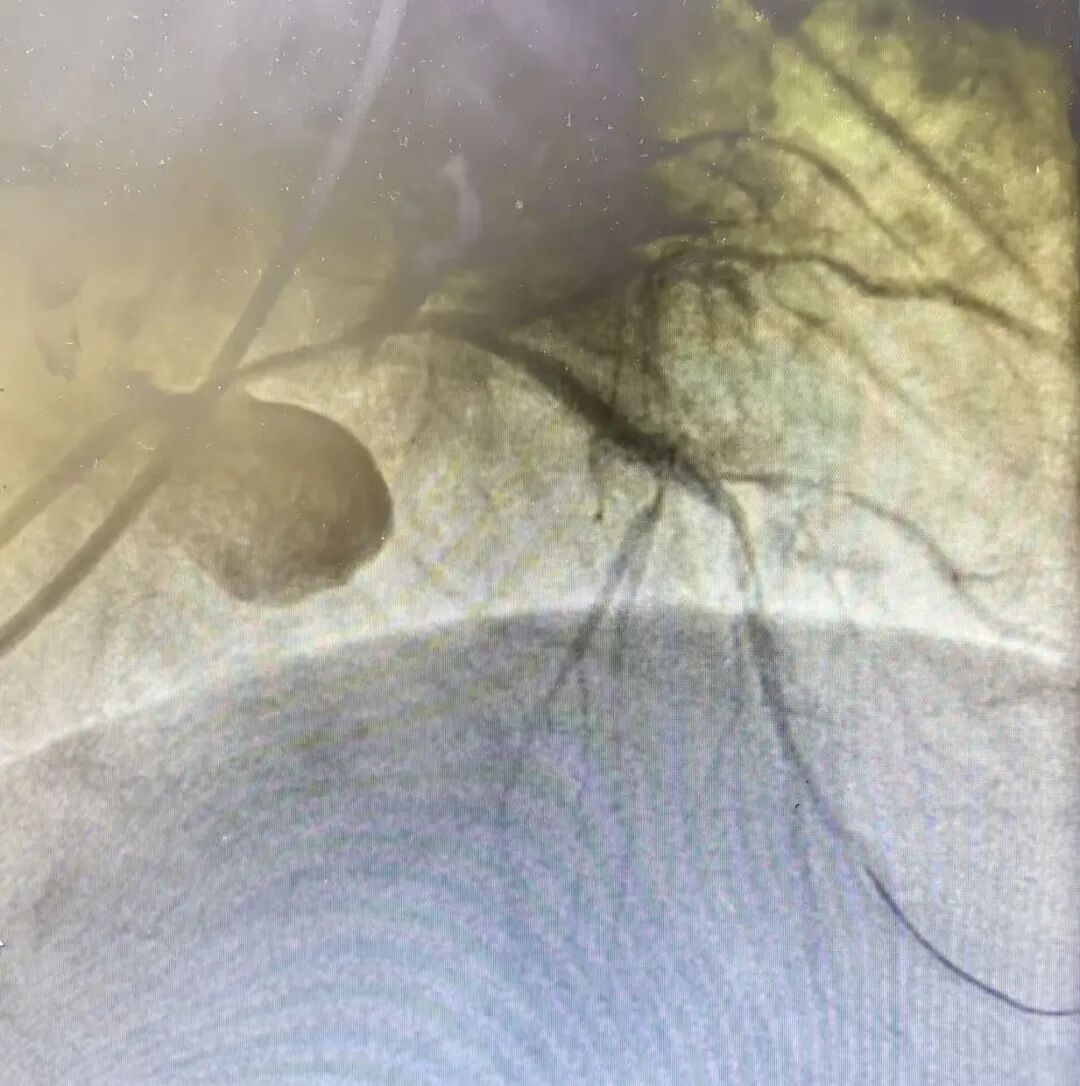

日照心脏病医院:这个团队,敢啃“硬骨头”!

当硬核技术遇上患者的信任,每一份托付都掷地有声。在IVUS指导下,当左主干至前降支处成功植入支架,瞬间打通堵塞血管、恢复血流,将许先生从死亡线上拉了回来。